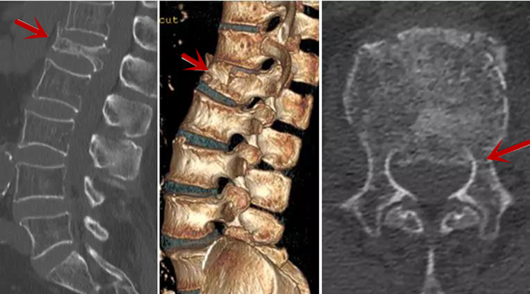

利器二:CT

CT利用X射線對(duì)人體檢查部位通過(guò)電腦切成若干層掃描,然后把每層的圖像都能顯示出來(lái)。CT相對(duì)于X光片具有更高的密度分辨力,可直接顯示X線片無(wú)法顯示的病變,觀察腰椎有無(wú)微小的骨折、骨質(zhì)有無(wú)破壞等骨質(zhì)情況、以及腰椎間盤(pán)突出、腰椎神經(jīng)根、椎管、椎間小關(guān)節(jié)的情況等。同時(shí)還可以通過(guò)后處理,重建腰椎矢狀位或冠狀位圖像,形成腰椎的3D圖像,更直觀地觀察病變部位,對(duì)腰椎手術(shù)風(fēng)險(xiǎn)具有提示作用,對(duì)手術(shù)方式的選擇具有指導(dǎo)意義,但是對(duì)神經(jīng)、脊髓損傷程度的顯示不如MRI,軟組織的分辨率仍有一定限制,對(duì)椎管內(nèi)病變顯示欠佳,且有一定的輻射。

從左向右依次為CT矢狀位重建圖像、三維重建圖像、軸位掃描圖像,箭頭提示腰1椎體爆裂性骨折